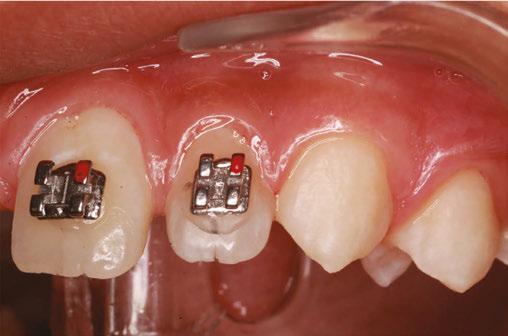

Treatment started with a transpalatal arch between the maxil lary first molars, which acted as a rigid unit to prevent unwanted facial inclination of the molars. A referral was made to an oral surgeon to remove the third molars. Fixed appliances of .022 x .028 Pinnacle® brackets with the McLaughlin, Bennett & Trevisi Prescription from Ortho Technology® were bonded to maxillary and mandibular teeth, and .014 thermal nickel-titanium fullform archwires (TruFlex®, Ortho Technology®, West Columbia, South Carolina) were used to align the arches after which a .016 stainless steel maxillary TruForce™ wire (Ortho Technology®) was placed. Following the stainless steel wire, two Vector TAS infrazygomatic miniscrews (Ormco™ Corporation, Orange, California) were inserted between the first and second maxillary molars (Figures 4A-4E).

Power chains with approximately 150 grams-force were added from the miniscrews to the maxillary first molars. After a .019 x .025 TruForce™ stainless steel archwire was placed in the maxillary arch, an additional power chain connected the maxil lary canines to the miniscrews to retract as well as to intrude the posterior buccal segments without jeopardizing the inclination of the maxillary anterior teeth. The patient refused the use of miniscrews in the mandibular arch, so molar bite blocks (Reli ance® Ultra Band-Lock, Ortho Technology®) controlled the ver tical position of the mandibular molars, which prevented them from over One-eightheruption.inch